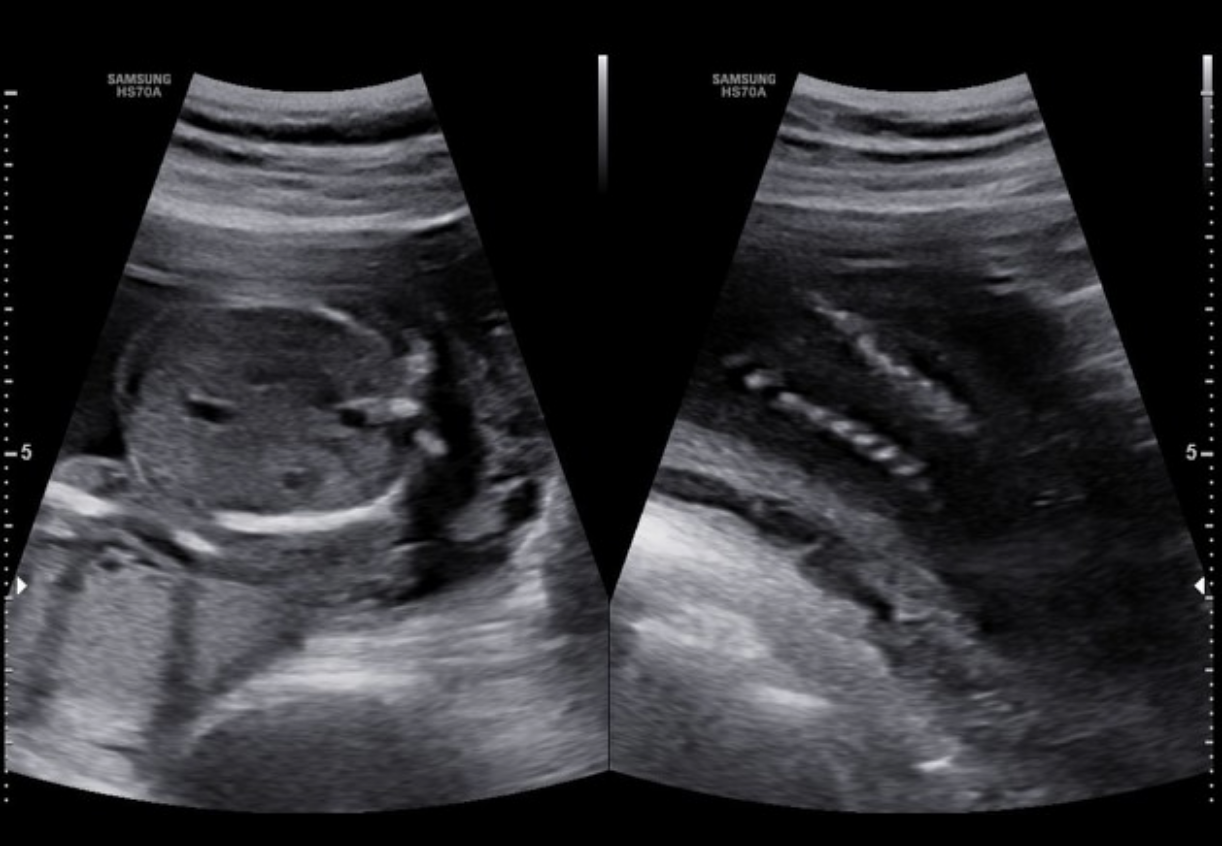

the color doppler portion shows

a) no pericallosal artery

b) thrombus of vein of galen

c) normal fetal anatomy

d) no circle of willis